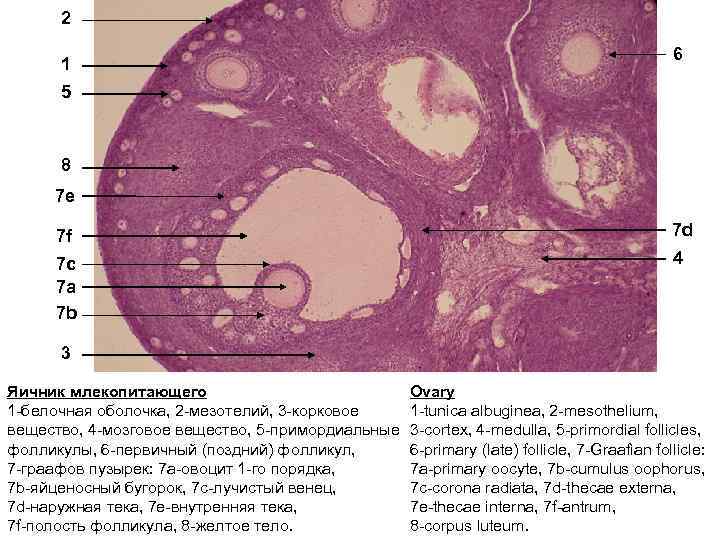

Созревание фолликула в яичнике: этапы и процессы

Раздел: Другие животные